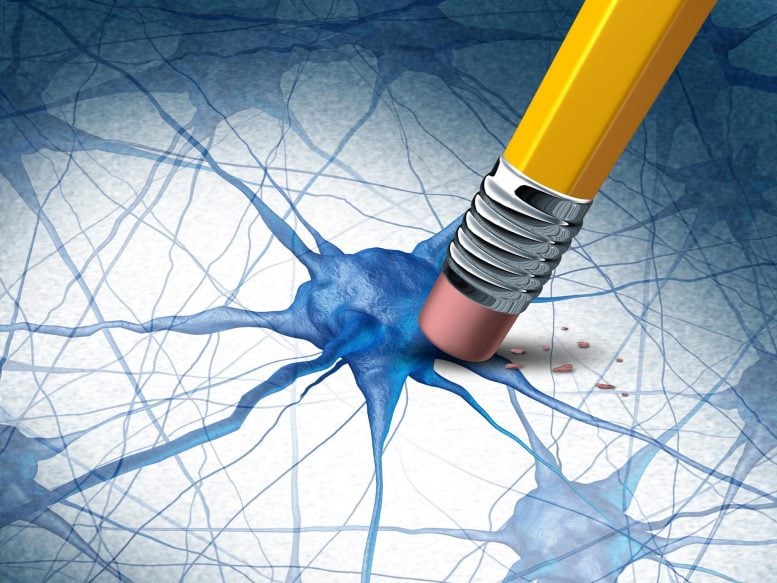

Latihan aerobik secara signifikan menurunkan penanda penyakit Alzheimer dan meningkatkan kesehatan otak, sehingga menawarkan strategi pencegahan yang menjanjikan. Para peneliti merencanakan uji coba pada manusia untuk memvalidasi temuan ini dan mengeksplorasi pengobatan baru. Penelitian baru yang dipimpin oleh para ilmuwan di Universitas Bristol (Inggris) dan Universitas Federal São Paulo (Brasil) menemukan bahwa latihan aerobik secara teratur dapat secara signifikan (…)